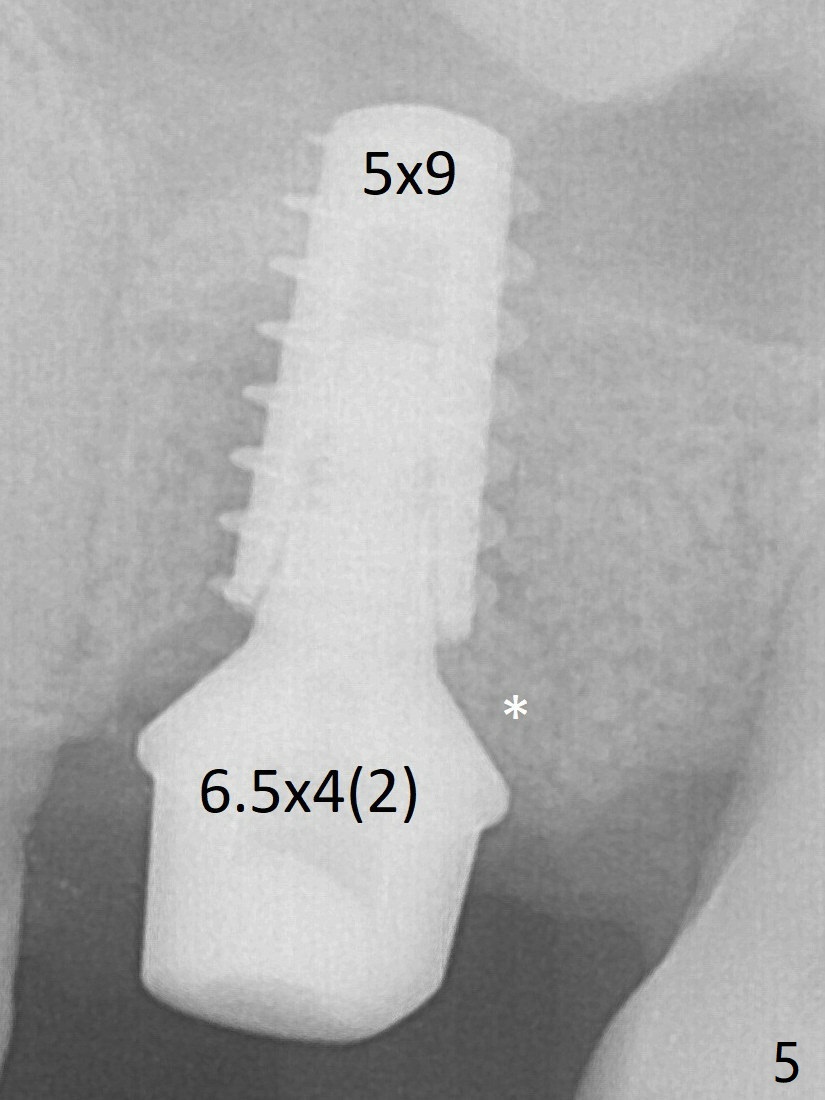

A 5x9 mm implant is placed slightly mesial; after placement of a 6.5x4(2) mm abutment and insertion of collagen plug in the palatal socket (radiolucent area distal to the implant), Vera graft is placed in the remaining socket space (Fig.5 *).  Nasal hemorrhage persists 1.5 months postop (Fig.6).   The distal gingiva is slightly tender and erythematous; a 6x4 mm healing abutment is placed 2.5 months postop (Fig.8).